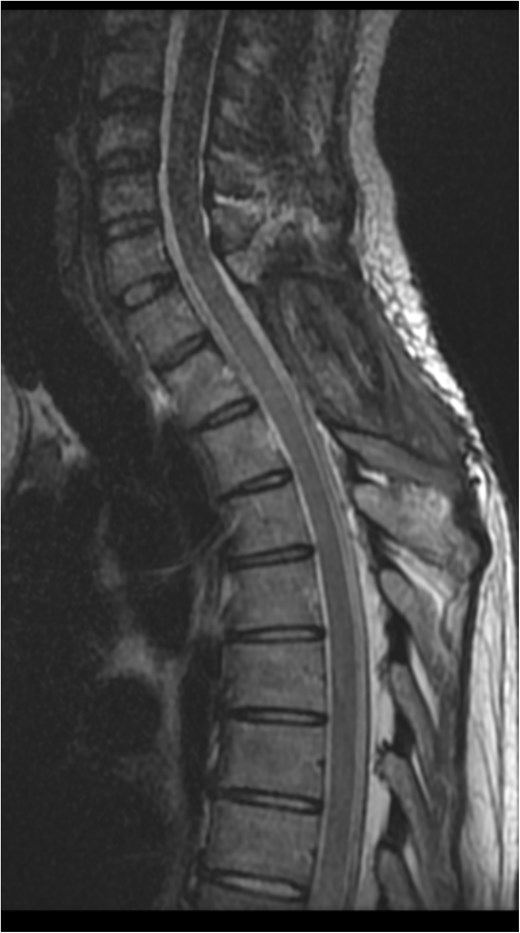

A 34-year-old female with no significant medical history and no regular medications presented to the emergency room with sudden onset of lower cervical to upper thoracic back pain radiating to the left shoulder. The symptoms rapidly progressed, leading to the loss of independent walking despite no prior trauma. Within hours, spastic paraplegia with sensory loss below the T1 level bilaterally developed. Initial blood tests were normal, including a complete blood count and coagulation profile. Total neuroaxis CT and thoracic spine CTA revealed a mass occupying the posterior aspect of the spinal canal between C7 and T2. Subsequent magnetic resonance imaging (MRI) indicated findings consistent with an acute spinal subdural hematoma causing cord compression, most pronounced at the C7-T2 level, without any changes in cord signal as shown in Fig. 1.

Preoperative MRI of the cervical spine. T1 (A) and T2 (B) sagittal views. Lesion is hyperintense (green arrow) on T1-weighted image and hypointense to isointense (blue arrow) on T2-weighted image at C7-T2 level.